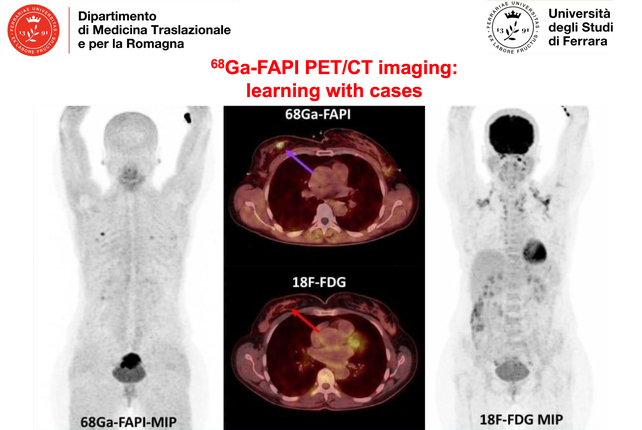

68Ga-FAPI PET/CT imaging:

learning with cases